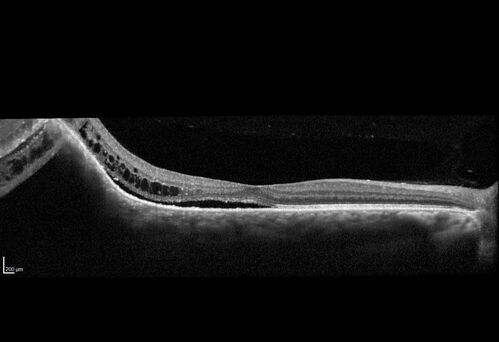

Choroidal Hemangioma Requiring PDT repeatedly

64 year old man.  Diagnosed with hemangioma in 2015.  PDT in 2016.  Images are from 2020 when fluid started to reaccumulate.  Needed PDT repeated two more times.

PDT treatments: [1] 2/19/2015 -  Pavan (IOP  problem after PDT)  AND [2] 11/2/21 PDT (7 mm temporal to fovea) - SMC  AND [3] 7/22/22 PDT 7.5 mm Temporal to the fovea